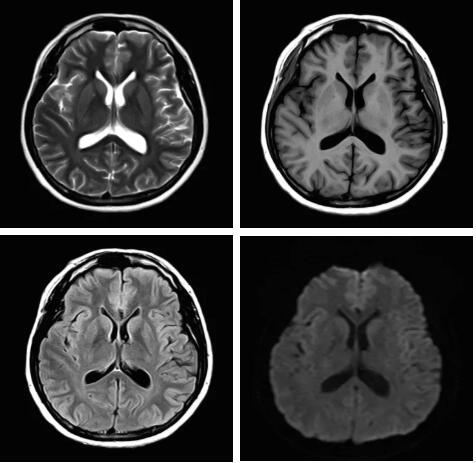

此技術(shù)主要用于神經(jīng)系統(tǒng)惡性腫瘤,以及其他腫瘤腦轉(zhuǎn)移瘤篩查。傳統(tǒng)情況下做腫瘤腦轉(zhuǎn)移篩查,很容易漏掉5mm以下小病灶,臨床發(fā)現(xiàn)后干預(yù)治療比較晚,要實(shí)現(xiàn)2mm高空間分辨率和超薄層全腦掃描在保證信噪比的情況下需要很長(zhǎng)時(shí)間大概十多分鐘,而且薄層增強(qiáng)序列顱內(nèi)血管呈高亮信號(hào),會(huì)干擾顱內(nèi)小病灶的觀察,血管和小病灶區(qū)分困難。佳能”螢火蟲(chóng)”成像技術(shù)既可以實(shí)現(xiàn)高空間分辨率和超薄層(最薄可實(shí)現(xiàn)0.2mm)全腦掃描,掃描時(shí)間短,2-3分鐘即可實(shí)現(xiàn)全腦3D掃描,同時(shí)避免了血管高亮信號(hào)的干擾,對(duì)顱內(nèi)原發(fā)或繼發(fā)的微小腫瘤檢查有重大意義。“螢火蟲(chóng)”成像技術(shù)具有磁敏感效應(yīng),對(duì)于亞急性血敏感敏感,可以區(qū)分出血和強(qiáng)化的腫瘤。